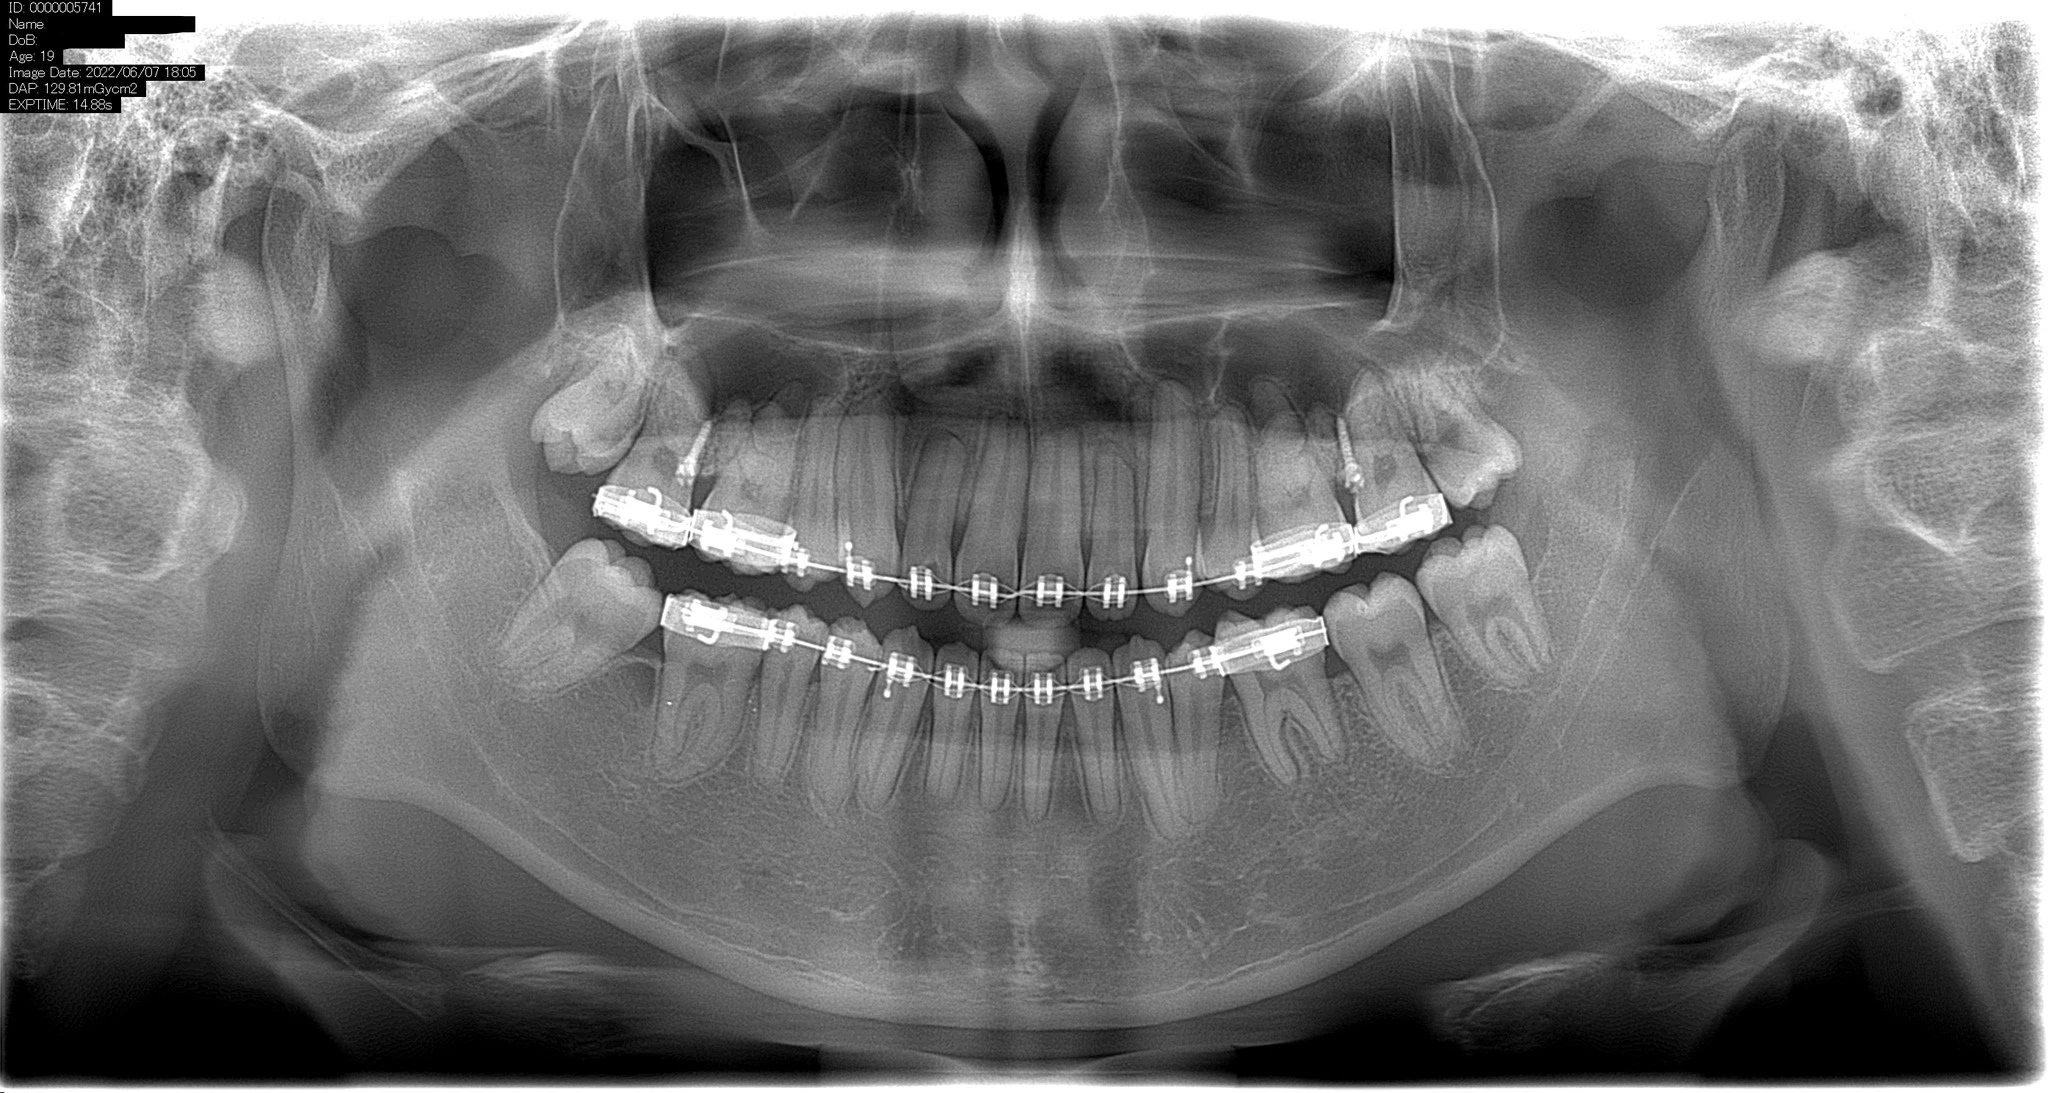

Phim X-quang toàn cảnh (còn được gọi là pantomography) là một kỹ thuật tạo một hình ảnh một lớp của các cấu trúc mặt bao gồm xương hàm trên và cung răng hàm dưới và những cấu trúc nâng đỡ chúng.

Phim x-quang toàn cảnh hầu hết là hữu ích trên lâm sàng để chẩn đoán những vấn đề cần sự quan sát tổng thể xương hàm. Những dẫn chứng thông thường bao gồm chấn thương, vị trí răng cối lớn thứ ba, bệnh lý xương và răng lan rộng, nghi ngờ những tổn thương lớn, sự phát triển của răng (đặc biệt là ở bộ răng hỗn hợp), những răng còn lại hoặc chóp chân răng (ở những bệnh nhân bất răng), đau khớp thái dương hàm và những bất thường do phát triển. Những chức năng này không đòi hỏi độ những hình ảnh có phân giải cao và sắc nét trong miệng.

Phim x-quang toàn cảnh thường được sử dụng để đánh giá hình ảnh ban đầu nhằm cung cấp thông tin cần thiết hoặc hỗ trợ để xác định nhu cầu chụp những hình ảnh khác. Phim toàn cảnh cũng hữu ích đối với những bệnh nhân không thực hiện chụp những phim trong miệng tốt được. Tuy nhiên, khi một loạt các phim chụp trong miệng có thể thực hiện được cho một bệnh nhân cần chăm sóc sức khỏe răng miệng tổng quát thì nhìn chung nếu chụp đồng thời thêm một phim toàn cảnh nữa sẽ có ít hoặc không có thông tin thêm nào từ nó.

Nhược điểm chính của phim x-quang toàn cảnh là hình ảnh không hiển thị những chi thiết giải phẫu nhỏ như ở him quanh chóp. Vì vậy, nó không hữu ích bằng phim x-quang quanh chóp khi muốn phát hiện những tổn thương sâu răng nhỏ, cấu trúc nhỏ của bờ mô nha chu, hoặc bệnh lý quanh chóp. Những bề mặt tiếp xúc của các răng cối nhỏ cũng thường bị chồng lên nhau. Do đó, việc thực hiện phim x-quang toàn cảnh ở một bệnh nhân trưởng thành thường không loại trừ nhu cầu chụp phim trong miệng để chẩn đoán những bệnh lý về răng thường gặp.

Những vấn đề khác liên quan đến phim x-quang toàn cảnh bao gồm sự phóng đại không bằng nhau và biến dạng hình học dọc theo hình ảnh. Đôi khi sự hiện diện của những cấu trúc chồng lên nhau có thể che lấp đi những tổn thương có nguồn gốc do răng, đặc biệt là vùng răng cửa. Hơn nữa, những điểm lâm sàng quan trọng có thể nằm ngoài mặt phẳng lấy nét (lớp ảnh) và có thể bị biến dạng hoặc hoàn toàn không hiển thị.